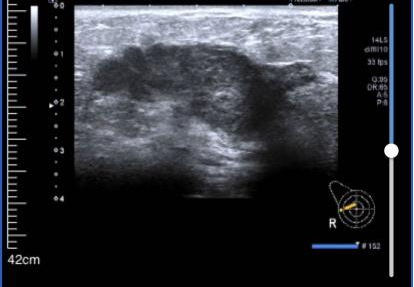

• 乳腺彩超:

1、右侧乳腺相当于9点钟方向距乳头约39.0mm腺体层内见范围约42.5*47.3*21.8mm不均质回声区,形态不规则,边界不清晰,内见丰富血流信号。其旁见大小约7.3*5.5mm低回声区,形态欠规则,边界欠清晰,内见强光点,内见少许血流信号。

2、右侧腋下见大小约31.0*15.8mm淋巴结影像,无正常淋巴门结构,形态尚规则,边界尚清晰,内见丰富血流信号。

超声提示:右侧乳腺实性肿块:BI-RADS 4C类;右侧腋下淋巴结肿大。

图1 乳腺彩超结果(2024-03-01)